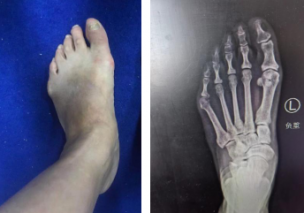

74岁奶奶踇外翻畸形10年,1cm小切口微创矫形助老人轻松行走

上周,徐州仁慈医院足踝科石荣剑副院长徐明亮主任团队采用第三代微创踇外翻矫形技术,为一位双足踇外翻畸形10年的74岁

详细 >>